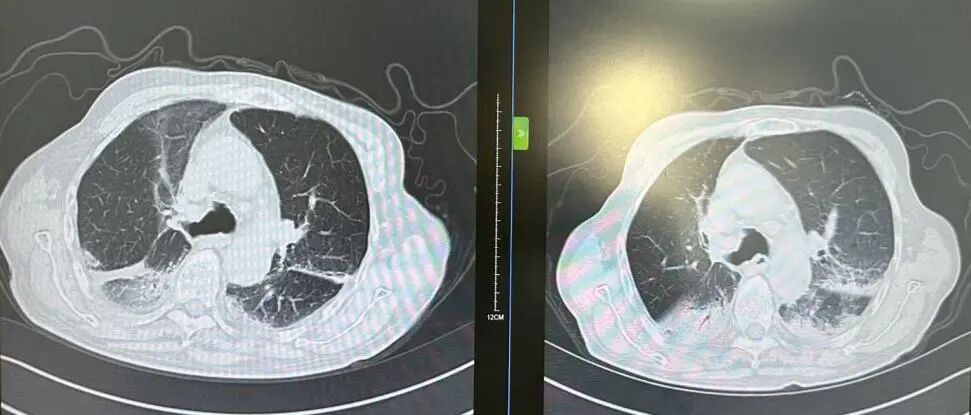

内容提要 近日,市第二人民医院呼吸与危重症医学科宋刚主任团队,成功救治一名98岁高龄、患有罕见隐源性机化性肺炎(COP)的患者。面对高龄、病情复杂、诊治风险高等重重困难,团队凭借精湛医术与丰富经验,帮助老人转危为安,再次彰显了科室在危重症救治领域的强大实力。 挑战一:高龄禁区,敢为人先 患者因发热、咳嗽,伴乏力、气短、喘息等症状来院,此前在当地诊所使用多种抗生素均无效,病因成谜。要明确诊断,支气管镜检查是关键一步,但对近百岁老人而言,此项操作犹如踏入“生命禁区”,风险极高。宋刚主任团队没有退缩,在全面评估、周密预案、充分沟通的基础上,凭借丰富经验成功实施检查,为后续治疗打开了至关重要的突破口。 治疗前患者肺部CT影像 挑战二:罕见病症,迷雾重重 检查结果指向一种罕见疾病——隐源性机化性肺炎(COP)。此病本就少见,好发于50~60岁人群,在近百岁老人中发生更是极为罕见。更为棘手的是,患者还伴有胸腔积液。COP通常表现为发热和肺部影像上的“游走性”阴影,很少合并胸腔积液,这使得诊断工作如雾里看花,难度倍增。 挑战三:病菌分辨,生死抉择 诊断刚明,新的考验接踵而至:患者标本中检出了根毛霉菌。COP的核心治疗是糖皮质激素,若根毛霉菌是致病菌,激素可能引发真菌扩散,用药无疑将导致致命风险。因此,辨别其是“定植菌”还是“致病菌”,成为治疗成败的关键。 宋刚主任团队凭借丰富的临床经验和严谨的诊疗思维,结合患者肺部影像特征、症状及化验结果,综合判断认为该霉菌属于定植菌,从而排除了治疗障碍,确保了后续用药安全。 精心施治,百岁老人转危为安 在后续治疗中,团队如履薄冰,精细平衡抗凝与激素治疗带来的出血、感染等风险,制定个体化方案。经过精心治疗与护理,老人肺部病灶显著吸收,各项指标恢复正常,最终康复出院。 治疗前后肺部CT影像对比,左侧为治疗后,右侧为治疗前。 此次成功救治,充分体现了市二院呼吸与危重症医学科在复杂疑难呼吸道疾病及危重症领域的综合救治能力。面对高龄高风险患者,团队始终以患者为中心,在风险与疗效间精准把握,用技术与责任守护每一位患者的呼吸健康。 人民医院 人民名医 宋刚 主任医师 ·葫芦岛市第二人民医院呼吸与危重症医学科主任 ·辽宁省生命科学学会东北呼吸与危重症医学(PCCM)分会辽宁省基层委员会副主任委员 ·辽宁省细胞生物学学会放射粒子治疗专业委员会理事 ·辽宁省抗击新冠肺炎疫情先进个人 ·辽宁省预防医学会第一届吸烟相关疾病防治专业委员会委员 ·葫芦岛市劳动鉴定委员会专家库成员 ·葫芦岛市医学会呼吸内科学分会第三届委员会副主任委员 专业特色:擅长呼吸系统疑难及急危重患者的救治,如急慢性支气管炎、支气管哮喘、慢性阻塞性肺疾病、肺炎、肺栓塞、肺癌、间质性肺疾病、睡眠呼吸暂停综合征等,尤其擅长有创无创机械通气、支气管镜下相关检查及治疗(TBNA、气道支架置入术、球囊扩张等)、全肺灌洗术等领先技术,发表国家级期刊多篇。 出诊时间:每周二、周四全天 出诊地点:门诊二楼东侧35诊室